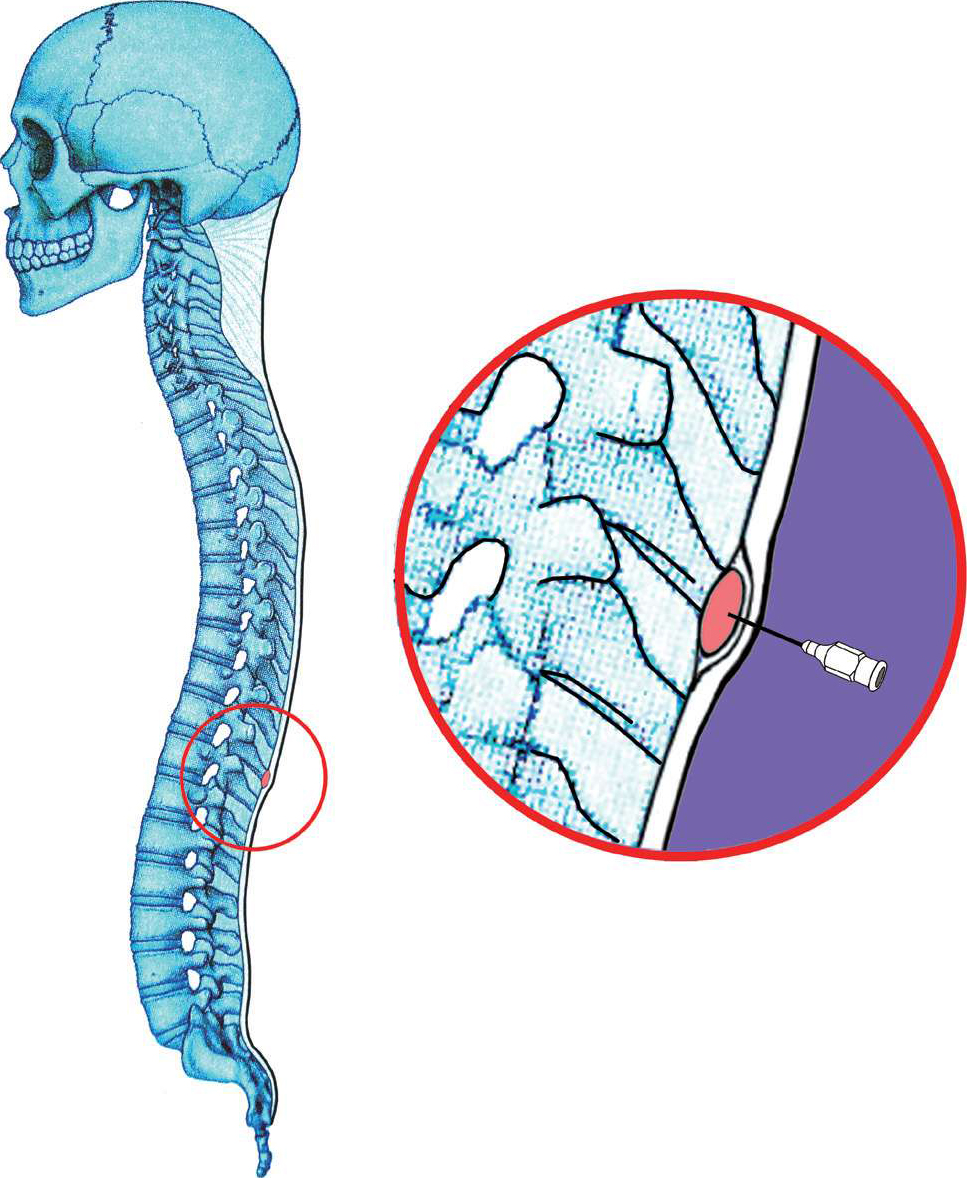

【应用解剖】

腰段脊神经根出椎间孔后,分成前支和后支,前支在上下两个横突之间向前、向下走行,后支向后绕过关节突至椎板后的肌肉层。夹脊穴封闭即将药液注入横突基部,横突间筋膜的前方,相当于脊神经根出椎间孔的部位,对脊神经前支和后支均起阻滞作用(图4-17、图4-18)。

3.具体操作 可采用单针法或三针法,进针点位于棘突旁3~4cm处(图4-19),向前、向内进针,触及第3、4、5腰椎横突下缘的骨组织后,再将针退出少许,改变方向,向下、向内至关节突外侧,于上、下横突之间刺入,穿过横突间韧带至脊神经根出椎间孔的部位(图4-20),开始注入每个间隙10ml的药液,共注3个间隙,双侧症状者可作双侧注药,单侧症状者也可只作单侧注药。

图4-20 进针点旁开棘突中线3.5cm,进针方向向前、向内,触及横突后,将针退出少许,改变方向,内倾角约为20°,向内、向下穿过横突间肌筋膜,针尖到达椎间孔外脊神经根周围注药即可